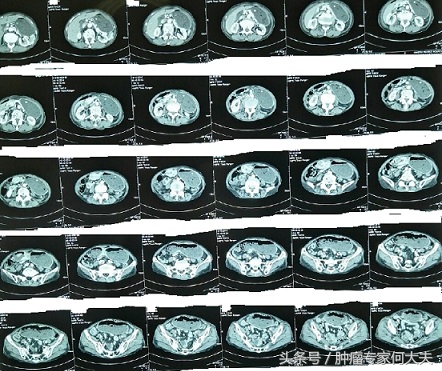

恶心呕吐没当回事,半年后被诊断为胃癌晚期 随着时间推移,原本清瘦的阿嬷越来越消瘦了,体力明显下降,再也不能像一年前从玉米地里挑些包谷米回家。国庆期间,在外打工的小儿子回到家里,知道母亲生病了,就带她去医院检查,在医院里医生给做了上腹部CT,结果甚为厉害,严重胃储留,时间长了胃扩张厉害,本来小小的胃,现在变得满肚子都是胃,下界到了盆腔。由于不停呕吐,医生给下了胃管,负压引流,胃胀呕吐明显减轻。